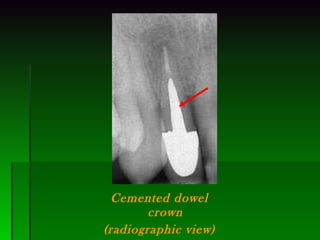

Cemented dowel crown (radiographic view)

Cemented dowel crown(radiographic view)